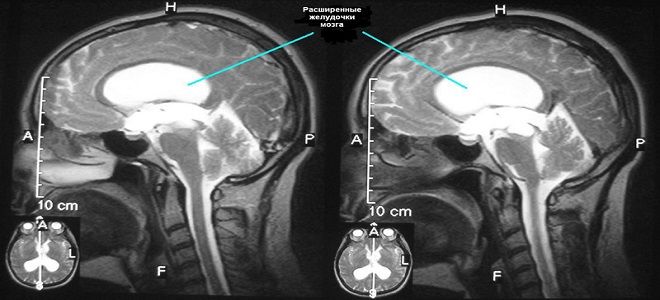

- Внутренняя гидроцефалия – характеризуется накоплением цереброспинальной жидкости в желудочках головного мозга.

Перед установлением диагноза необходимо провести полное обследование пациента. Внешнюю гидроцефалию можно определить визуально, обратив внимание на изменения в размере головы и формах черепа, тогда как внутреннюю гидроцефалию головного мозга можно выявить с помощью МРТ. Тем не менее, окончательный диагноз может быть поставлен только после анализа данных аппаратного обследования: